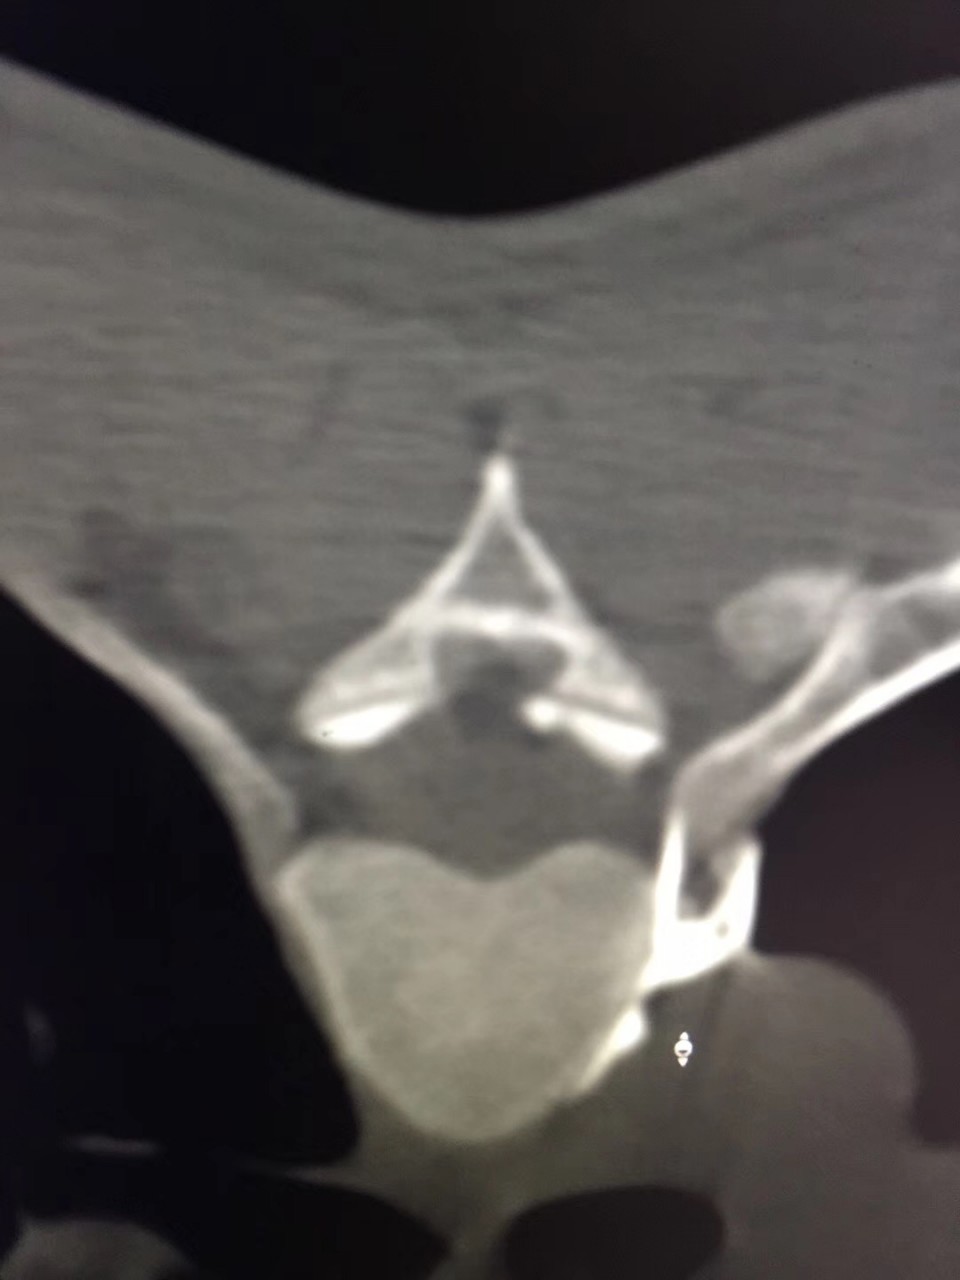

近日,疼痛科接诊了一位18岁的多汗症患者,该患者反复双足发汗多年,伴手上皮肤脱落。曾就诊于省内外多家医院,但均未获得满意的疗效。听闻安徽医科大学第一附属医院疼痛科是一种以微创介入方法治疗各种疑难病痛的科室,遂前往就诊。疼痛科副主任医师宋阳在对该患者病情特点进行综合的分析后决定对其进行CT引导下胸交感神经链无水酒精化学毁损术。当日手术结束后该患者立马感觉到双手不再是以前那样冰冷,逐渐回复了正常的温度,且发汗症状完全消失。在观察了数日之后无任何的复发症状,负责该患者的副主任医师宋阳称,通过无水酒精的化学毁损作用中断汗腺神经分泌的神经传递过程,可永久的减少出汗,达到临床治愈水平。

对于诊断明确的原发局部性多汗症患者,传统的治疗手段有局部及全身药物治疗以及激光、微波等物理疗法。目前比较主流的有CT引导下经皮穿刺胸交感神经化学阻滞及外科手术治疗。其中CT引导下交感神经链阻滞技术成功率甚至可达100%,治疗效果与胸腔镜下交感神经链切断术效果相当,应用无水酒精能达到对交感神经链的功能有效长久的阻滞,达到良好的治疗效果,且创伤更小、并发症更少。胸腔镜下交感神经切断术是治疗手、头面部及腋窝多汗症的一种二线治疗方案。但其术后疼痛、气胸、神经病变累及上肢、霍纳综合症以及代偿性多汗症发生率较高。